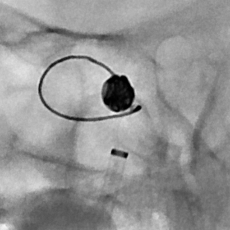

啥也别说了,赶紧去做脑血管造影备治疗吧,结果发现颅内一个炸弹💣(颅内动脉瘤),而且长在一个不太容易破裂的部位(床突旁),形状也不太规则,上面还有一个细长的小泡(破裂点),破裂机制:这个破裂小口,多次小量出血,通过反复的脑脊液循环大部集聚到了腰大池,出现了颅内几乎看不到啥异常而腰大池内为血性不凝脑脊液的巨大反差,血液在蛛网膜下腔进一步刺激神经根,才导致了脖子疼和腰疼~~~,但是,这是脑动脉瘤反反复复破裂出血导致的哦,细思极恐………